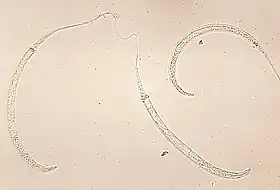

| Larva de Dracunculus medinensis | |